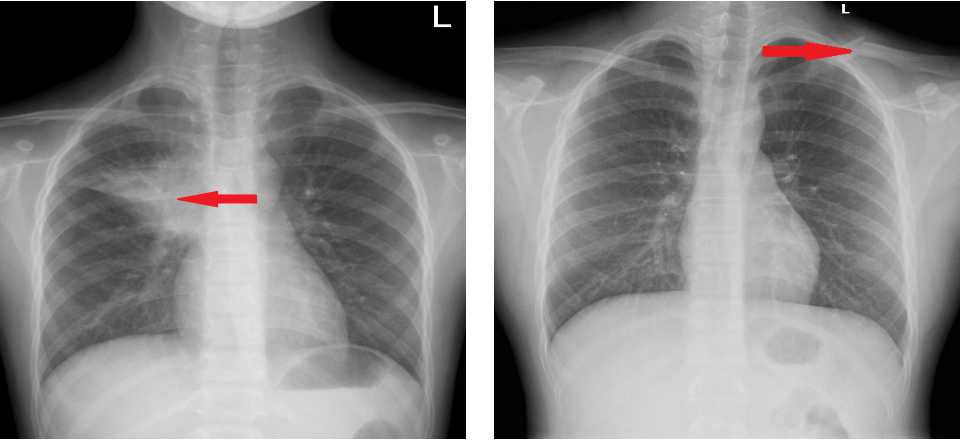

左起:图1a图1b

图1a胸部正位,右肺上叶肺炎;图1b胸部正位,左侧锁骨骨折